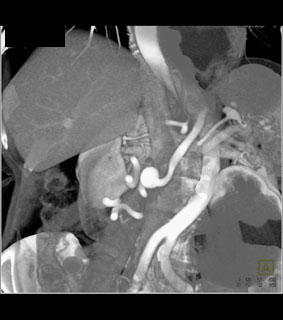

The best dx in this case is?

GDA aneurysm